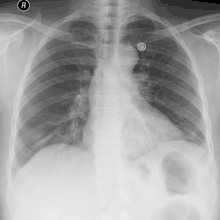

При фізикальному обстеженні ослаблений дихальний звук під час аускультації та приглушений (гіпосонорний) звуку під час перкусії над емпіємою плеври є типовими, але неспецифічними ознаками. Для підтвердження діагнозу зазвичай вистачає звичайного рентгенологічного обстеження грудної порожнини. Емпієми плеври характеризуються явним зниженням прозорості на рентгенологічному знімку. Скупчення гною проявляється у вигляді «дзеркала» з достатньо чітким рівнем на рентгенограмі.